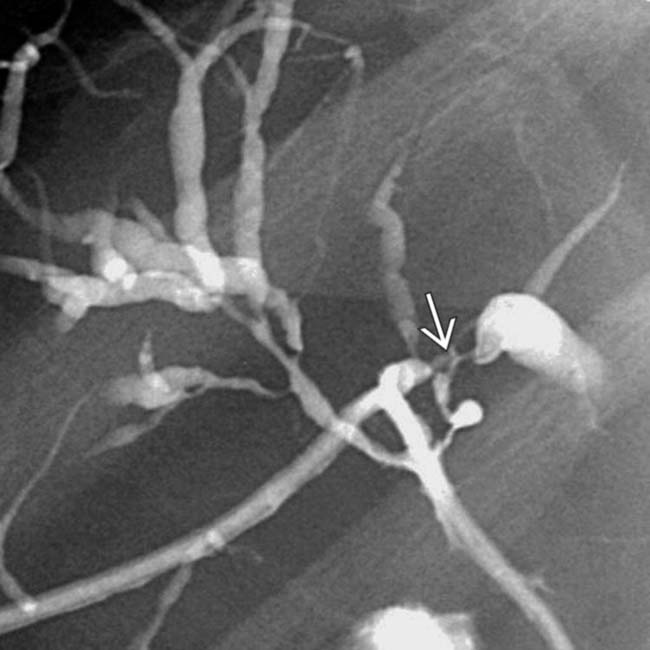

Appearance of PSC on CT. ac There is irregular dilatation of the Beaded Appearance Of Bile Duct beaded appearance of the cbd as well as the intrahepatic biliary radicles with multiple strictures alternating with focal dilatations. the appearance of terminal bile ducts varies, particularly on ercp, and overinterpretation is common. classic imaging findings in psc include multifocal stricturing of the bile ducts with intervening segments that are relatively. biliary strictures, also called bile. Beaded Appearance Of Bile Duct.

From fity.club